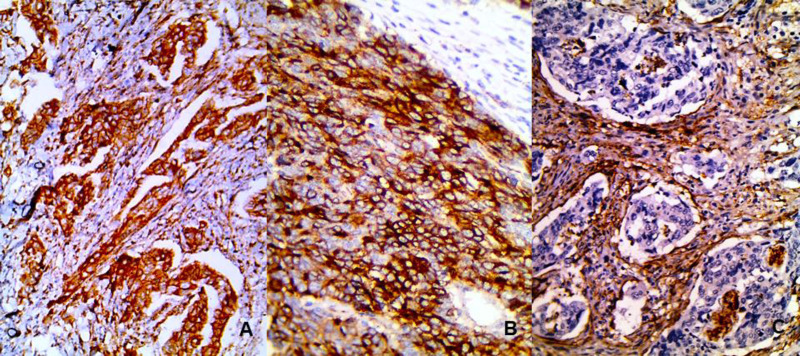

Methods: This retrospective study included 100 cases of colorectal carcinoma that were immunohistochemically stained using Notch1 and CD10 antibodies. Expression of Notch1 and CD10 was evaluated and compared with different clinicopathological parameters.

Results: Notch1 expression was detected in the tumor and stromal cells in 92% of the cases, while CD10 expression was seen in 31% of tumor cells 79% of stromal cells of the included cases. Their expressions in tumor cells were significantly associated with higher grade (P=0.029 and 0.001), deeper invasion (P=0.01 and 0.002), advanced stage (P=0.012 and 0.001), and distant metastasis (P=0.001 and 0.02). Notch1 expression was positively correlated with CD10 expression (P=0.018). Both Notch1 expression and high CD10 expression in the stromal cells were associated with short overall survival (P=0.003 and 0.01).

Conclusion: CD10 and Notch1 may have roles in colorectal carcinoma progression via induction of tumor invasion, metastasis and impairment of tumor response to therapy. CD10 and Notch1 could be used as biomarkers for aggressive CRC and may be considered for future target therapy.